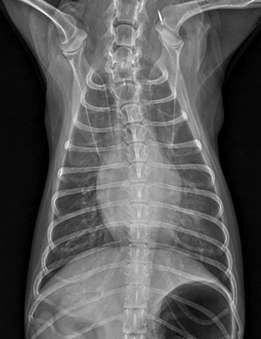

아래는 아이의 엑스레이 사진입니다.

검게 보여야 할 폐의 부분이 하얗게 보입니다, 더하여 방사선상 심장의 크기도 커 보입니다.

그렇습니다. 심장병에 의한 폐부종입니다.